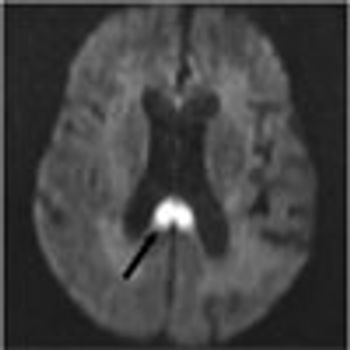

A 68-year-old woman with a history of hypertension, hyperlipidemia, and tobacco use presented with her third stroke in the past 7 years. Neurological deficits included dysarthria and left-sided motor and sensory loss. A previous transthoracic echocardiogram with a bubble study did not reveal any cardiac source of embolism. Axial MRI of the brain on admission showed an abnormal signal in the bilateral hemispheres representative of multiple subacute infarcts